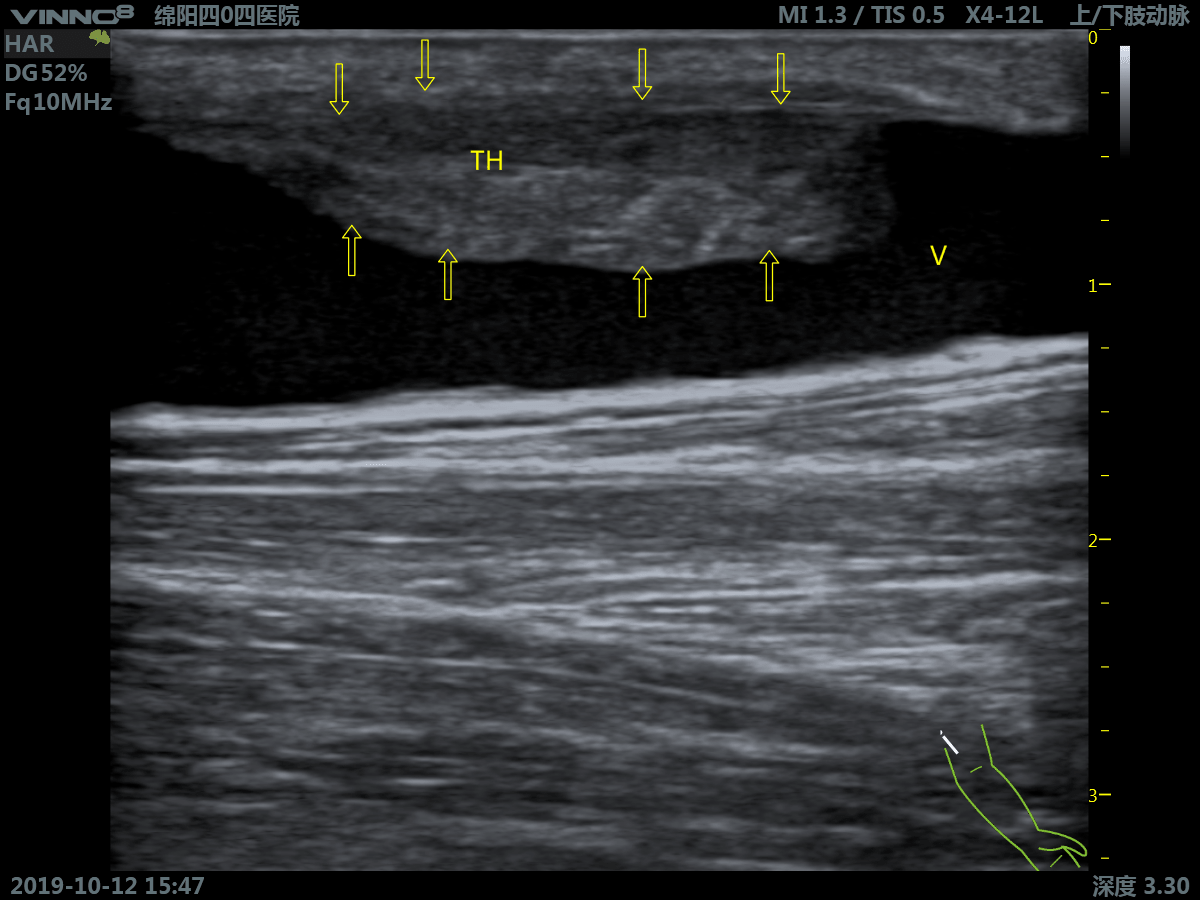

Портативный ультразвуковой сканер VINNO 8

Преимущества портативного УЗИ аппарата VINNO 8

- инновационная платформа RF обеспечивает суперчистое изображение в результате сверхвысокой скорости обработки данных

Клиническое применение:

- периферические сосуды